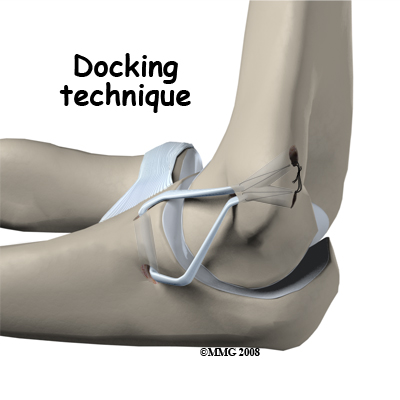

One common technique used to replace the damaged ulnar collateral ligament is called the docking technique. The surgeon drills two holes in the ulna and three in the medial epicondyle ( the small bump of bone on the inside of the elbow at the end of the humerus). The two holes in the ulna form a tunnel that the tendon graft will be looped through. The three holes in the medial epicondyle form a triangle. The bottom hole will be bigger than the top two holes, so that the surgeon can slide the end of the tendon graft into the bottom hole. The two top holes are used to pull the tendon graft into the tunnel using sutures that are attached to the graft and threaded through the two holes.

After the tendon is harvested, sutures are attached to both ends. The tendon is looped through the lower tunnel formed in the ulna, and stretched across the elbow joint. The two sutures attached to the ends of the graft are threaded into the larger bottom tunnel in the medial epicondyle and each is threaded out one of the upper, smaller holes.

Using these two sutures, the surgeon pulls the end of the graft farther into the upper tunnel until the amount of tension is correct to hold the joint in position. The surgeon carefully puts the elbow through its full arc of motion and readjusts the tension on the sutures until he is satisfied that the proper ligamentous tension is restored. The two sutures are tied together to hold the tendon graft in that position.

Using these two sutures, the surgeon pulls the end of the graft farther into the upper tunnel until the amount of tension is correct to hold the joint in position. The surgeon carefully puts the elbow through its full arc of motion and readjusts the tension on the sutures until he is satisfied that the proper ligamentous tension is restored. The two sutures are tied together to hold the tendon graft in that position.